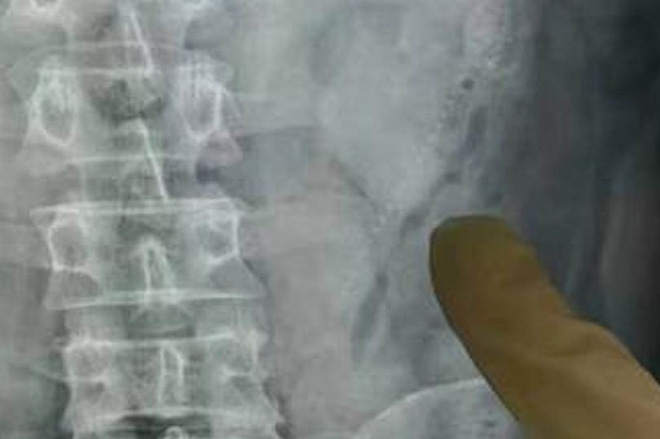

Các bác sĩ tại Quảng Châu (Trung Quốc), đã phẫu thuật thành công lấy ra hai con cá sau khi tiến hành chụp tia rơn-gen kĩ thuật số vùng bụng để xác định vị trí của chúng. Họ cho biết một con đã làm thủng thành ruột của nam bệnh nhân, gây ra cơn đau bụng khủng khiếp của anh.

Các bác sĩ đã tìm thấy “vật thể lạ” và lấy nó ra sau khi nam bệnh nhân đến khám trong tình trạng ho ra máu.